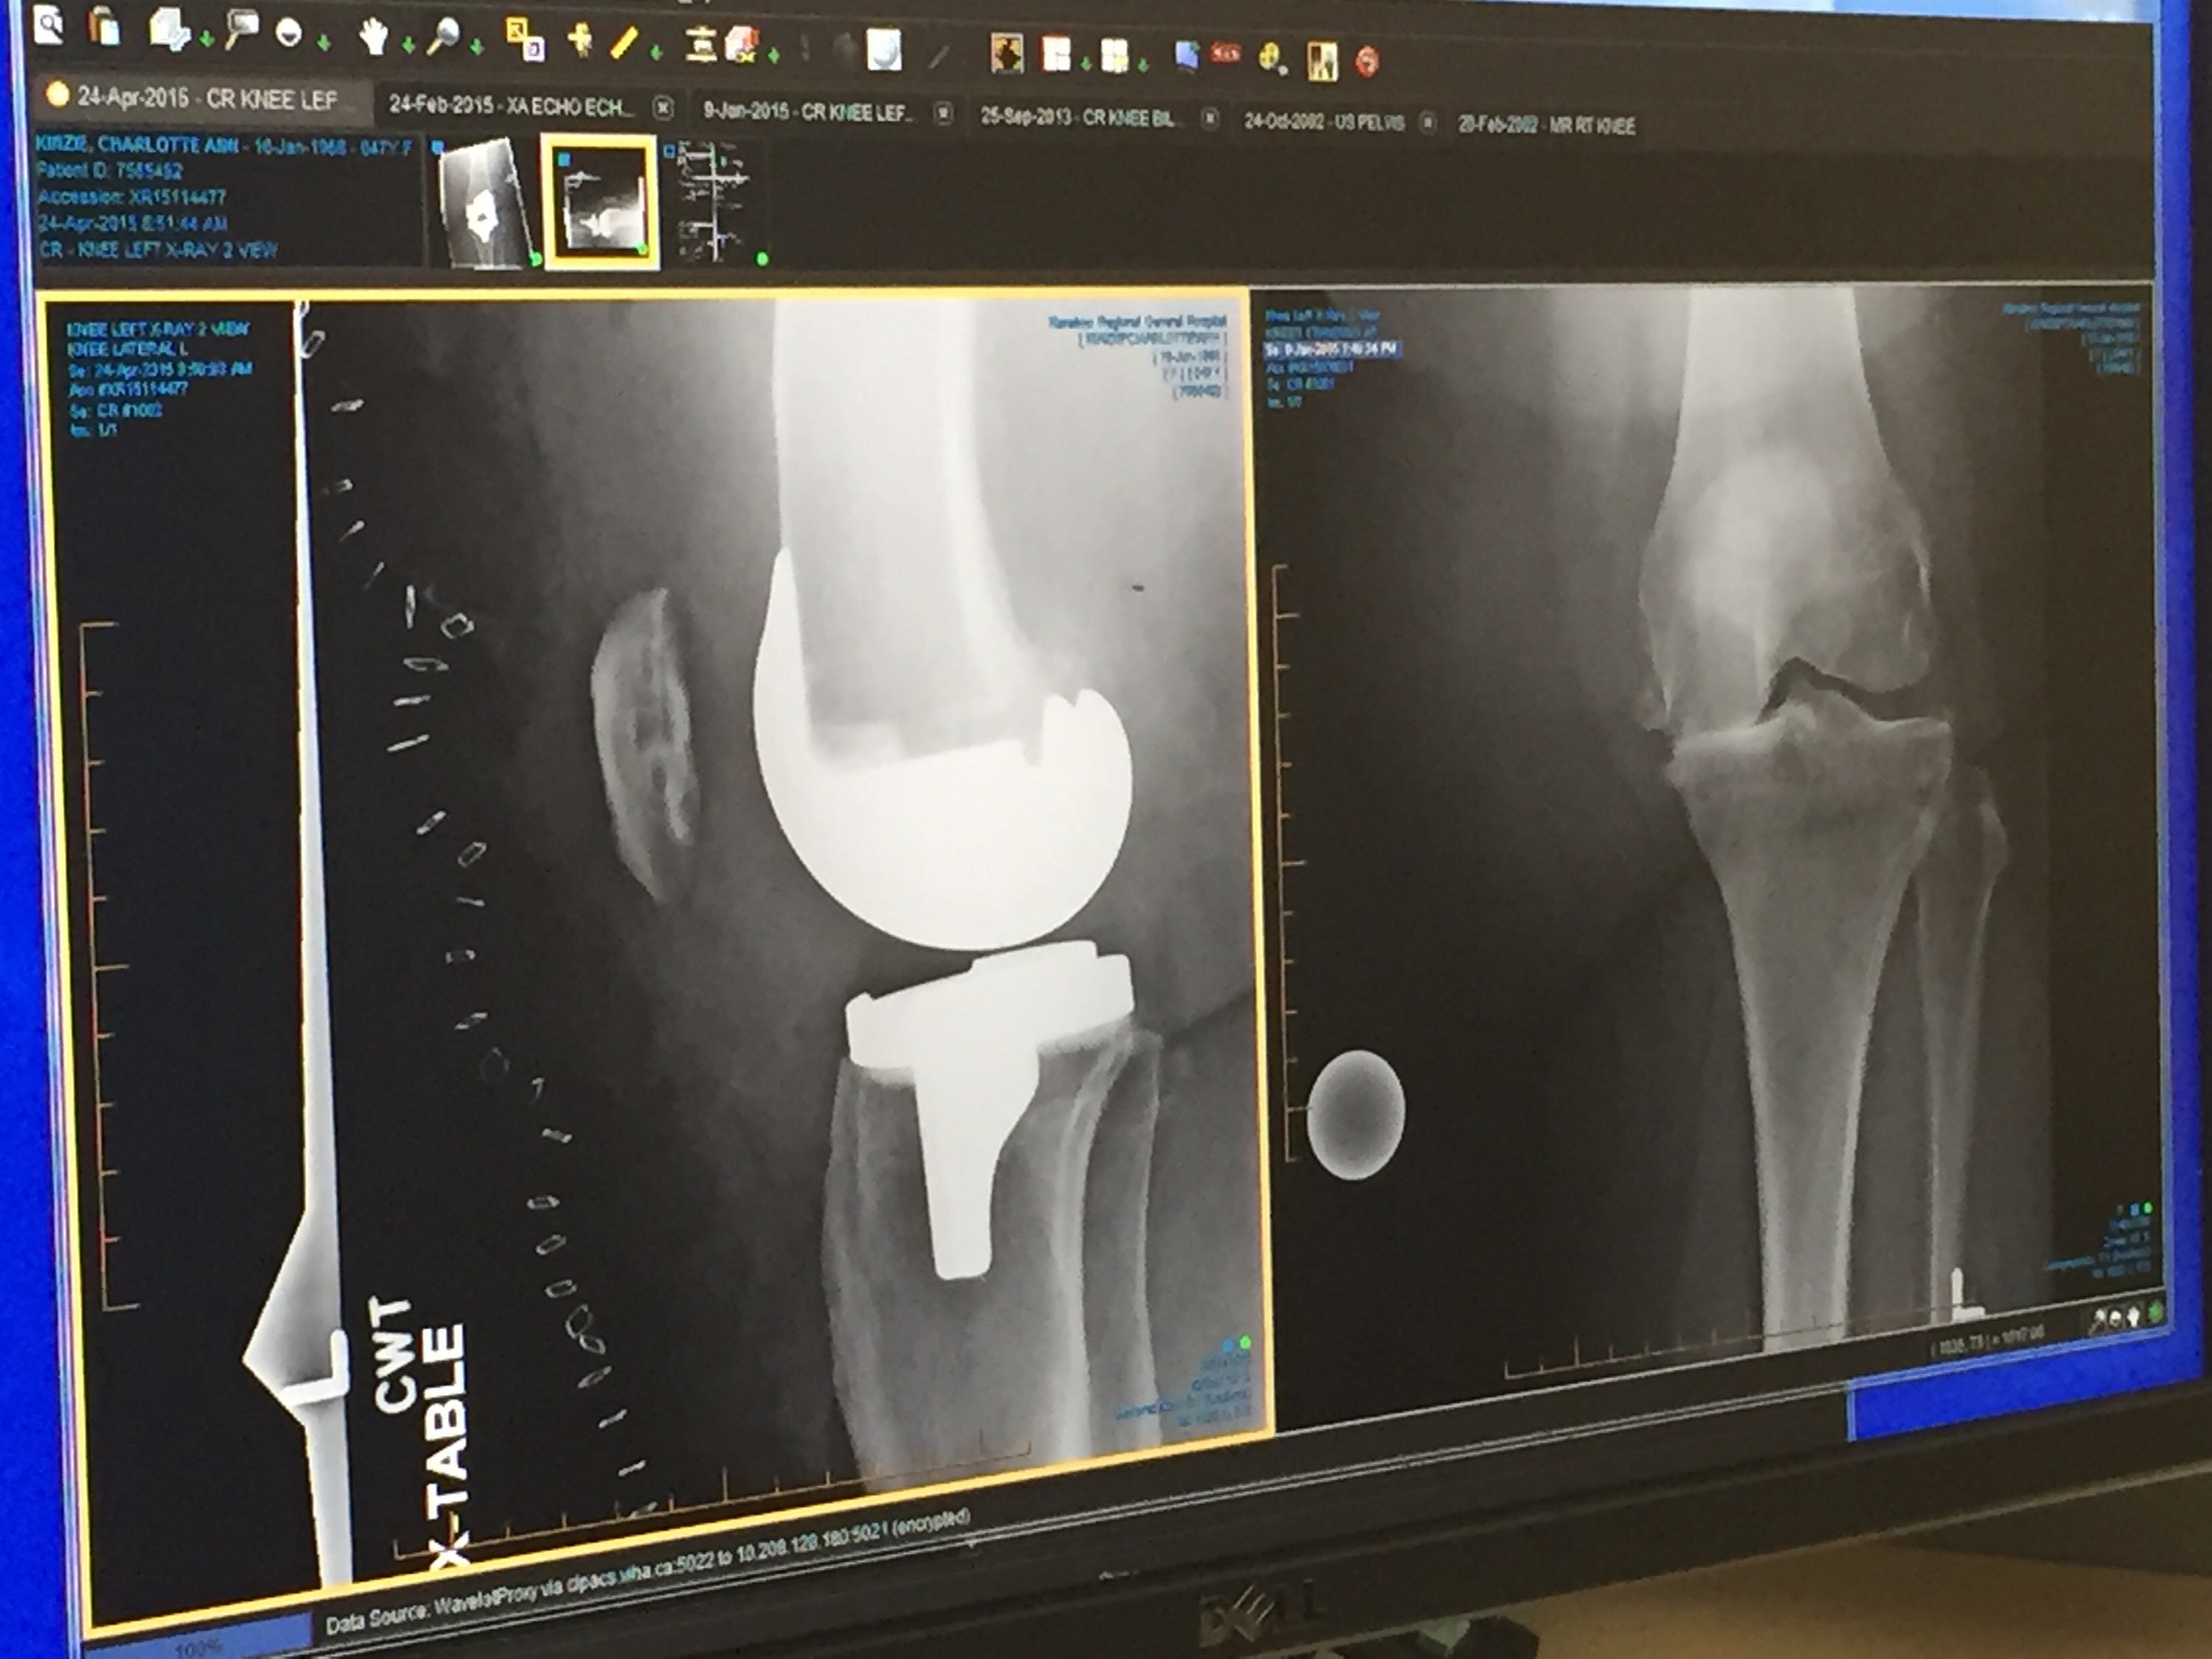

I finally have one new knee. I’ve been needing both of them replaced for over five years. Finally, on April 22 Dr Cobus Smith replaced my left knee. IMG_3959He’s a great surgeon and a very nice man with a good sense of humour. I know! Unusual for a surgeon.